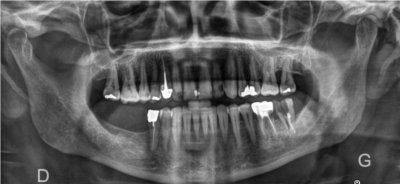

Images de panoramiques dentaire: